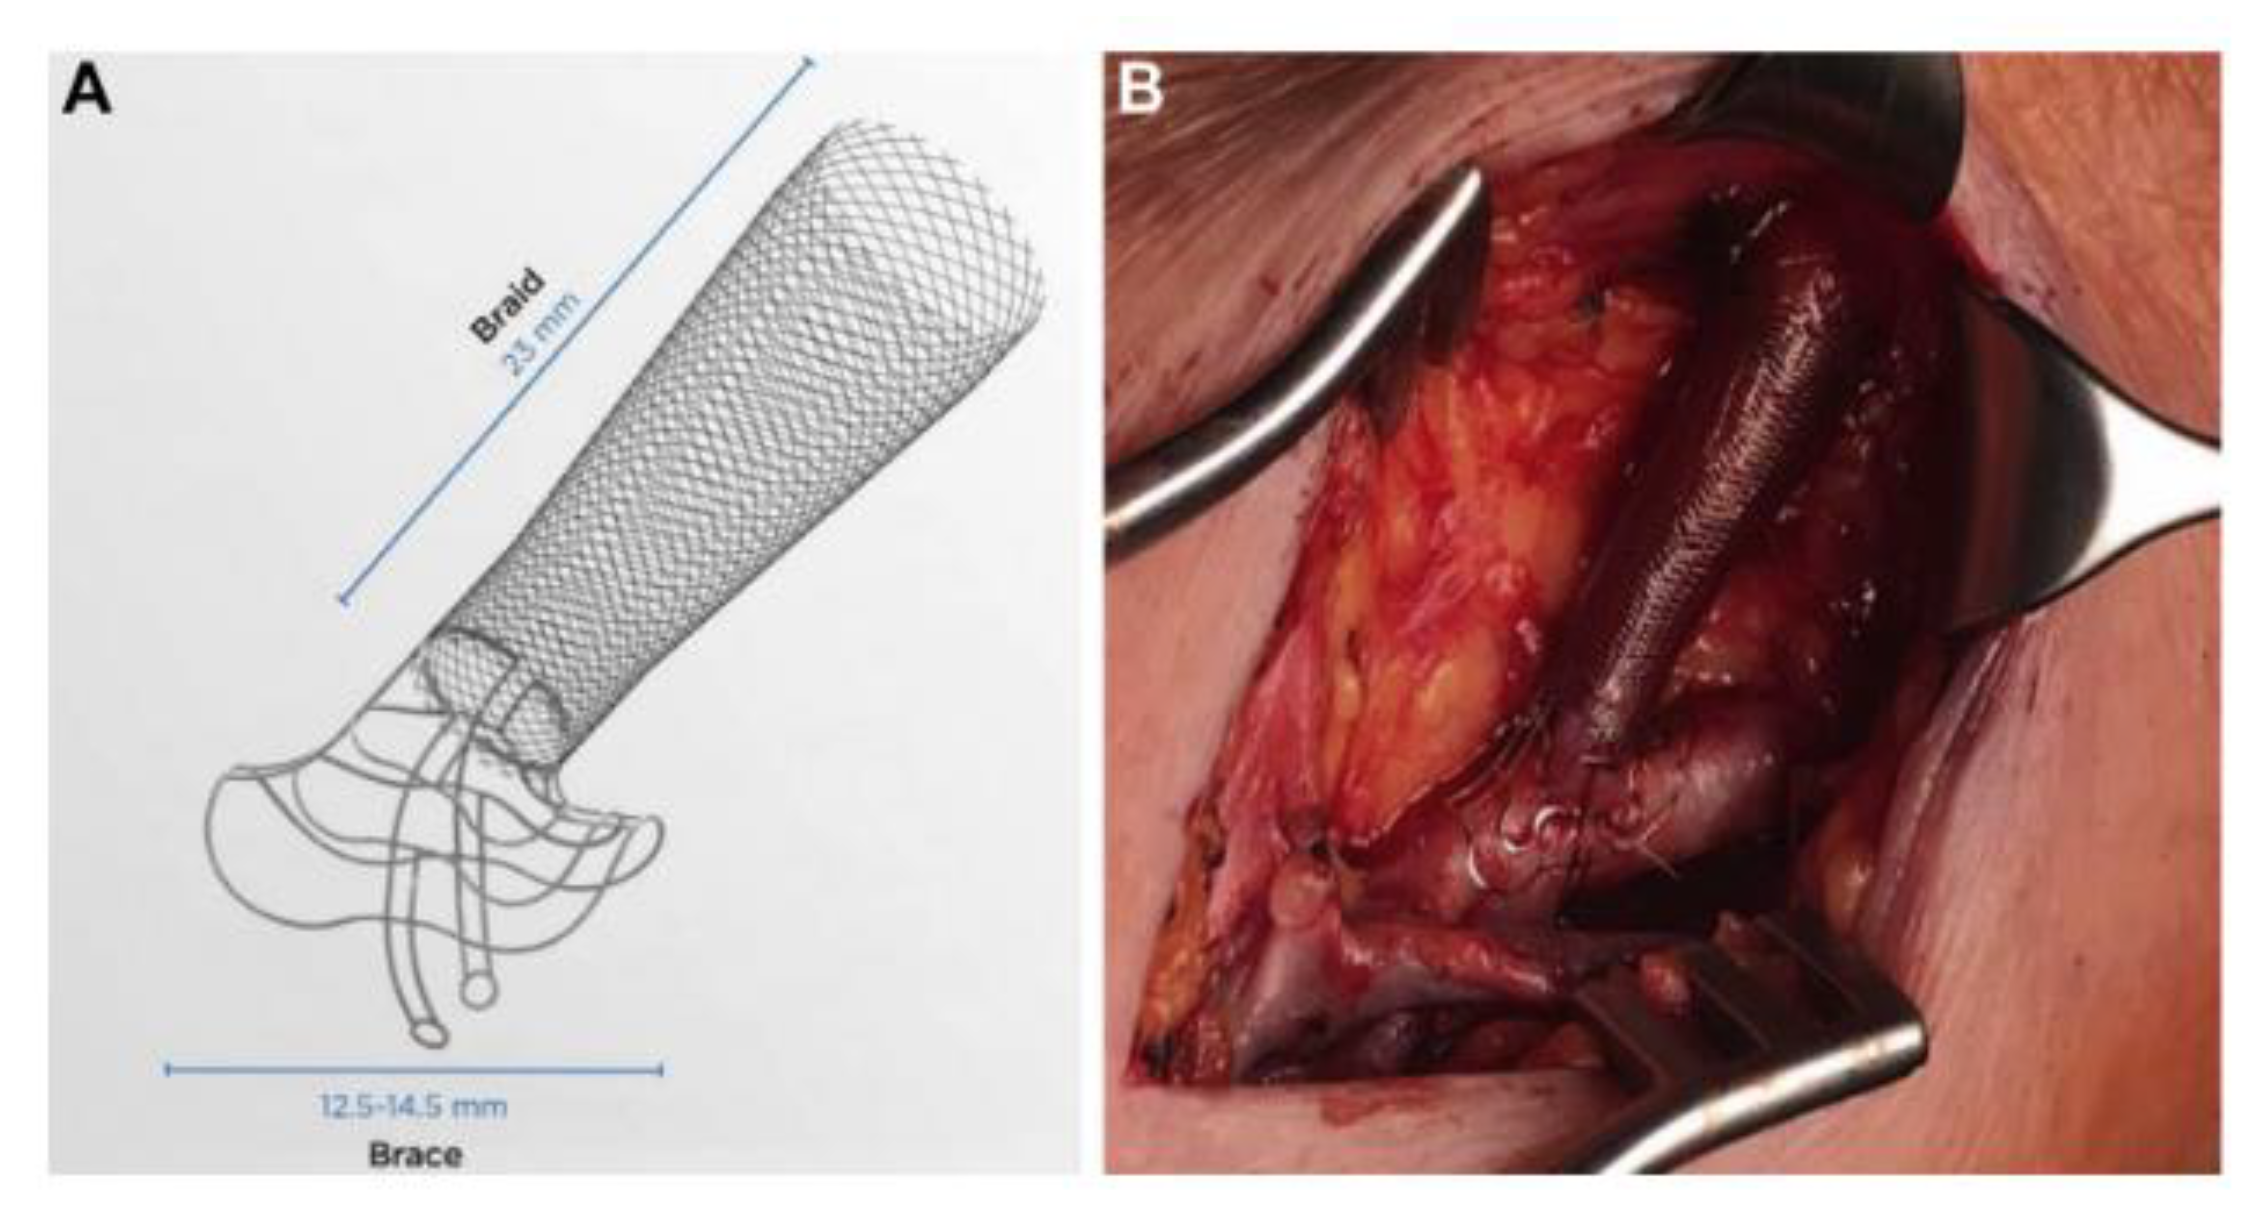

4.1. Mechanical Devices

| Mechanical device | VasQ | Clinical (Phase 1/2) | Significantly increased venous luminal diameters at three and six months and increased functional patency at six months following brachiocephalic fistula formation | Karydis et al. (2020) [50] |